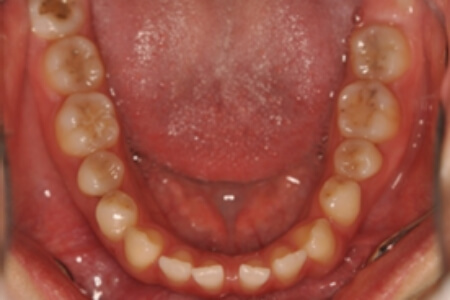

すきっ歯・正中隔離(非抜歯)【0625】

初診時

年齢

21歳 性 別 女性

治療期間 1年9か月 費 用 矯正施術料:900,000円

調整料:4,000円/月

治療内容の詳細 初診時21歳の女性で、上顎前歯部の隙間(正中離開)を主訴として来院されました。

検査の結果、上下顎前歯部に空隙を伴うアングルⅠ級不正咬合と診断しました。

治療としては、非抜歯の上、マウスピース矯正装置(インビザライン)で配列を行いました。

治療期間は、1年9か月でした。